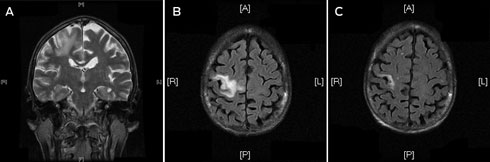

A frail 68-year-old woman of European ancestry presented to the emergency department with partial seizures of her left hand and mild left hemiparesis. Magnetic resonance imaging (MRI) scans of the brain revealed a non-enhancing lesion in the right precentral gyrus that was thought to represent infarction (Box, A and B).

After surgery, the patient began highly active antiretroviral therapy (HAART) with a regimen comprising Trizivir (abacavir, lamivudine and zidovudine) and ritonavir-boosted indinavir. She experienced symptomatic improvement, weight gain and reduced partial seizures within a few weeks. The plasma HIV viral load was undetectable within 8 weeks of commencing HAART and a repeat MRI scan at that time confirmed a significant reduction in size of the cerebral lesion (Box, C).